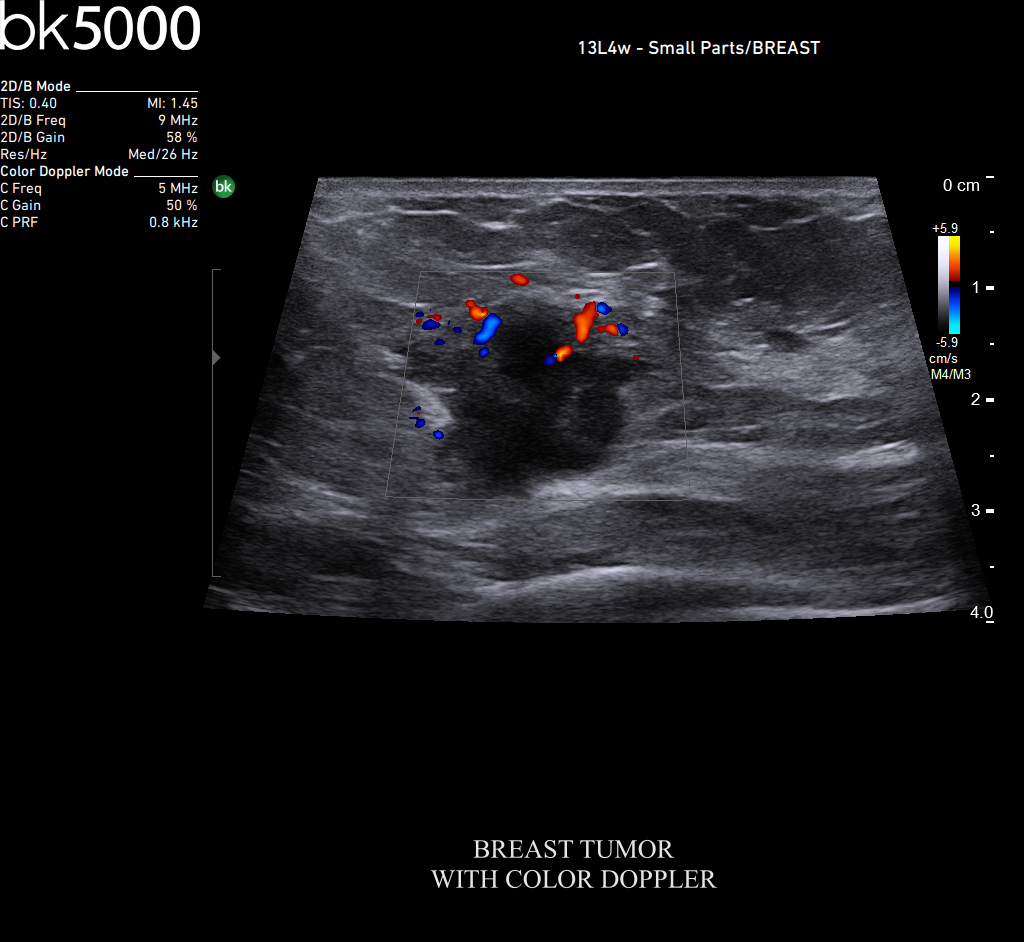

You know what you need, and you need it fast. That’s why the bk5000 is designed to deliver the high resolution images you count on quickly and efficiently. Whether you’re identifying margins of a lesion or making a general assessment of an area of interest, the bk5000 has the power and performance to meet your needs on your terms.

From the simplest diagnostic imaging to the most critical interventional procedures, every clinical situation has its own set of unique challenges. The bk5000 offers a full suite of innovative technologies and advanced controls and adjustments to help you achieve the best possible image quality, across many applications.